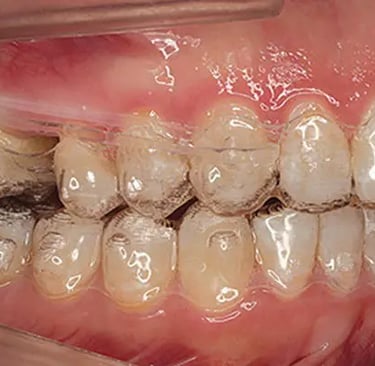

Molar distalization involves moving molars backward to create space for alignment or improve occlusion. This movement can inadvertently alter the vertical dimensions of the jaw, leading to unwanted changes like molar extrusion or open bites. Vertical control ensures the molars remain in the desired position vertically, maintaining harmony in the bite and facial aesthetics.

Aligners can minimize extrusion forces on molars, reducing the risk of open bites. Their snug fit and planned pressure distribution help maintain the vertical stability of teeth.Sequential Tooth Movement:

Strategically placed attachments can enhance the aligner's grip on molars, improving the precision of distalization and vertical control.

In cases where greater control is required, TADs are often used alongside aligners. These small, screw-like devices provide a stable anchor point, minimizing unintended movements during molar distalization. Here's how they contribute:

TADs prevent molar extrusion by anchoring adjacent teeth or structures, ensuring the molars only move distally.Skeletal Adjustments: